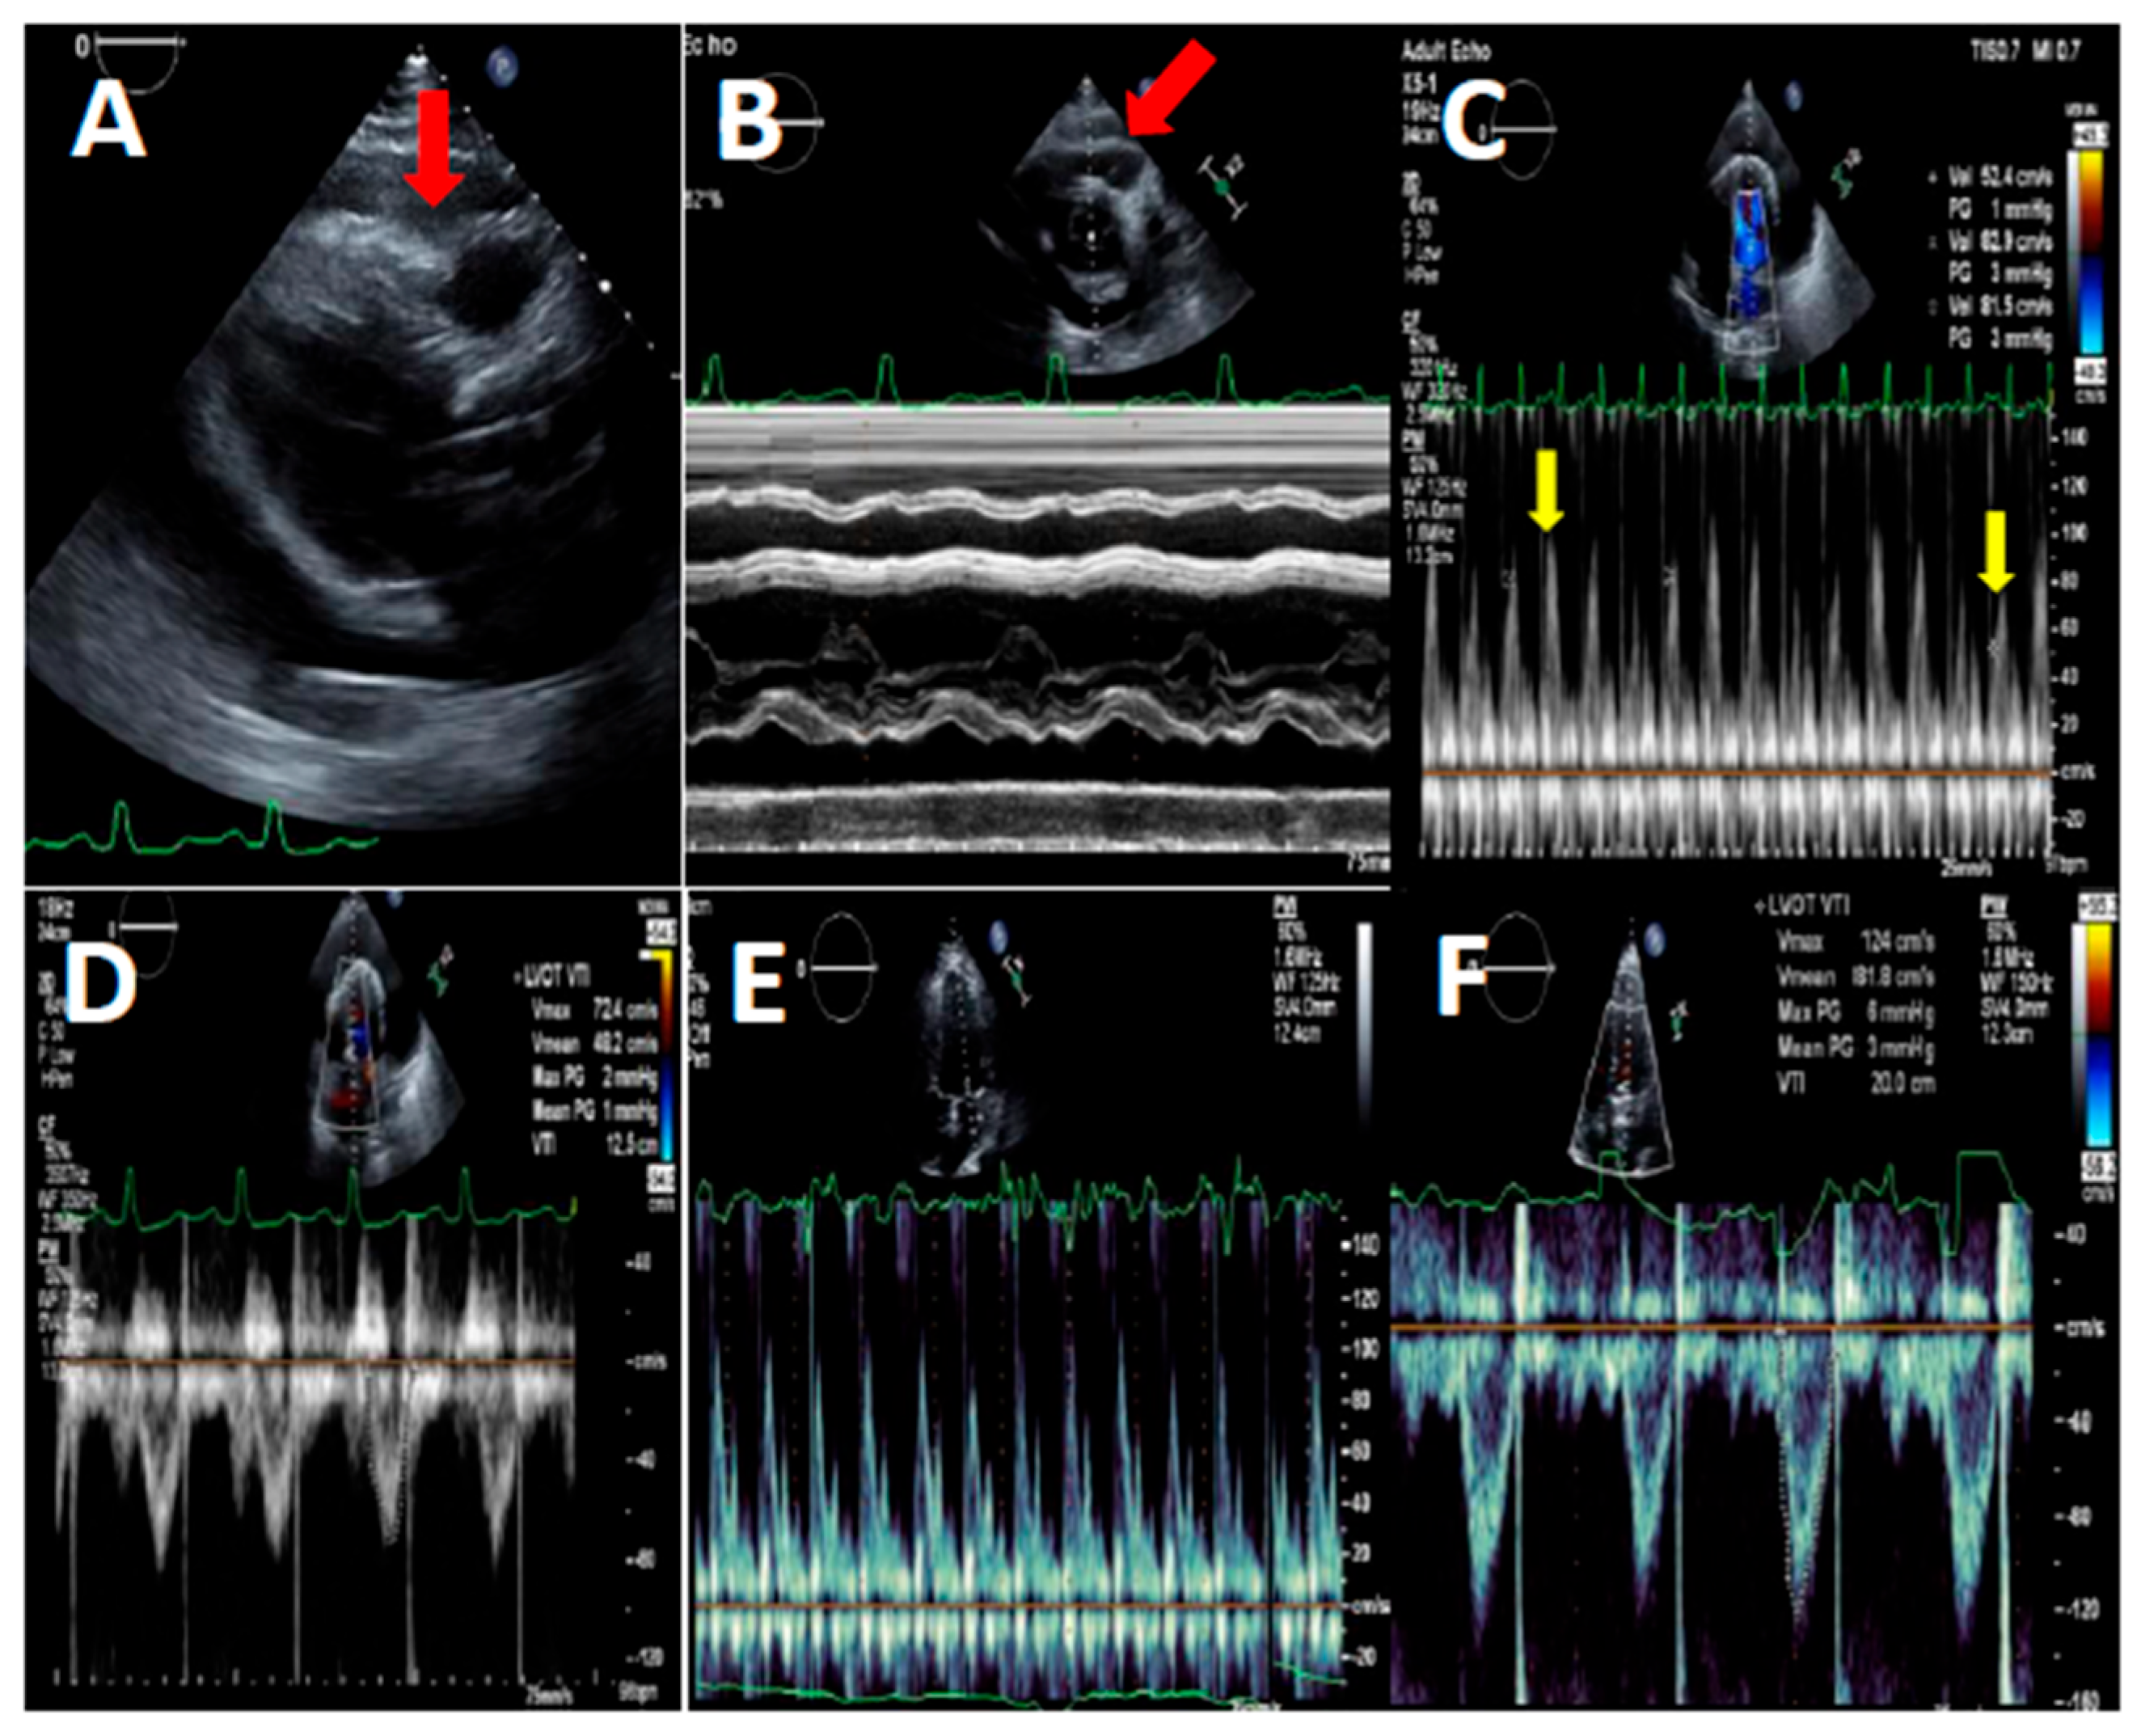

Pericardiocentesis was defined as needle aspiration of pericardial fluid or any surgical procedure involving drainage of pericardial fluid, including surgical pericardiotomy and pericardial window (Figure 1). Patient records with ICD code of pericardiocentesis, pericardiotomy or pericardiectomy were thoroughly reviewed by the investigators, to ensure that drainage of pericardial fluid was performed.

Left ventricular function and effusion size were determined by echocardiography (Figure 2). All studies were done by experienced sonographers and were interpreted by senior cardiologists specialized in echocardiography [8,9]. All studies were done with VIVID E3 95 Ultrasound device manufactured by General Electric and were held following standard protocol of the American Society of Echocardiography guidelines.

Figure 2. Transthoracic echocardiography of a COVID-19 patient before (panels A-D) and after pericardiocentesis (panels E-F) (A) - Parasternal long axis view, diastolic RV free wall collapse (red arrow) due to high pressure in the pericardial space due to circumferential large pericardial effusion. (B) - Short axis view M-Mode at the level of aortic valve showing diastolic collapse of RV free wall (red arrow). (C) - Apical 4-chamber view PW Doppler of the mitral flow showing respiratory variations between beats (yellow arrows). (D) - Apical 4-chamber view PW Doppler of the left ventricular outflow tract systolic flow showing low VTI, indicating low stroke volume. (E) - Apical 4-chamber view PW Doppler of the mitral flow showing normalization of mitral flow pattern. (F) - Apical 4-chamber view PW Doppler of the LVOT systolic flow showing normal VTI, indicating normal stroke volume.